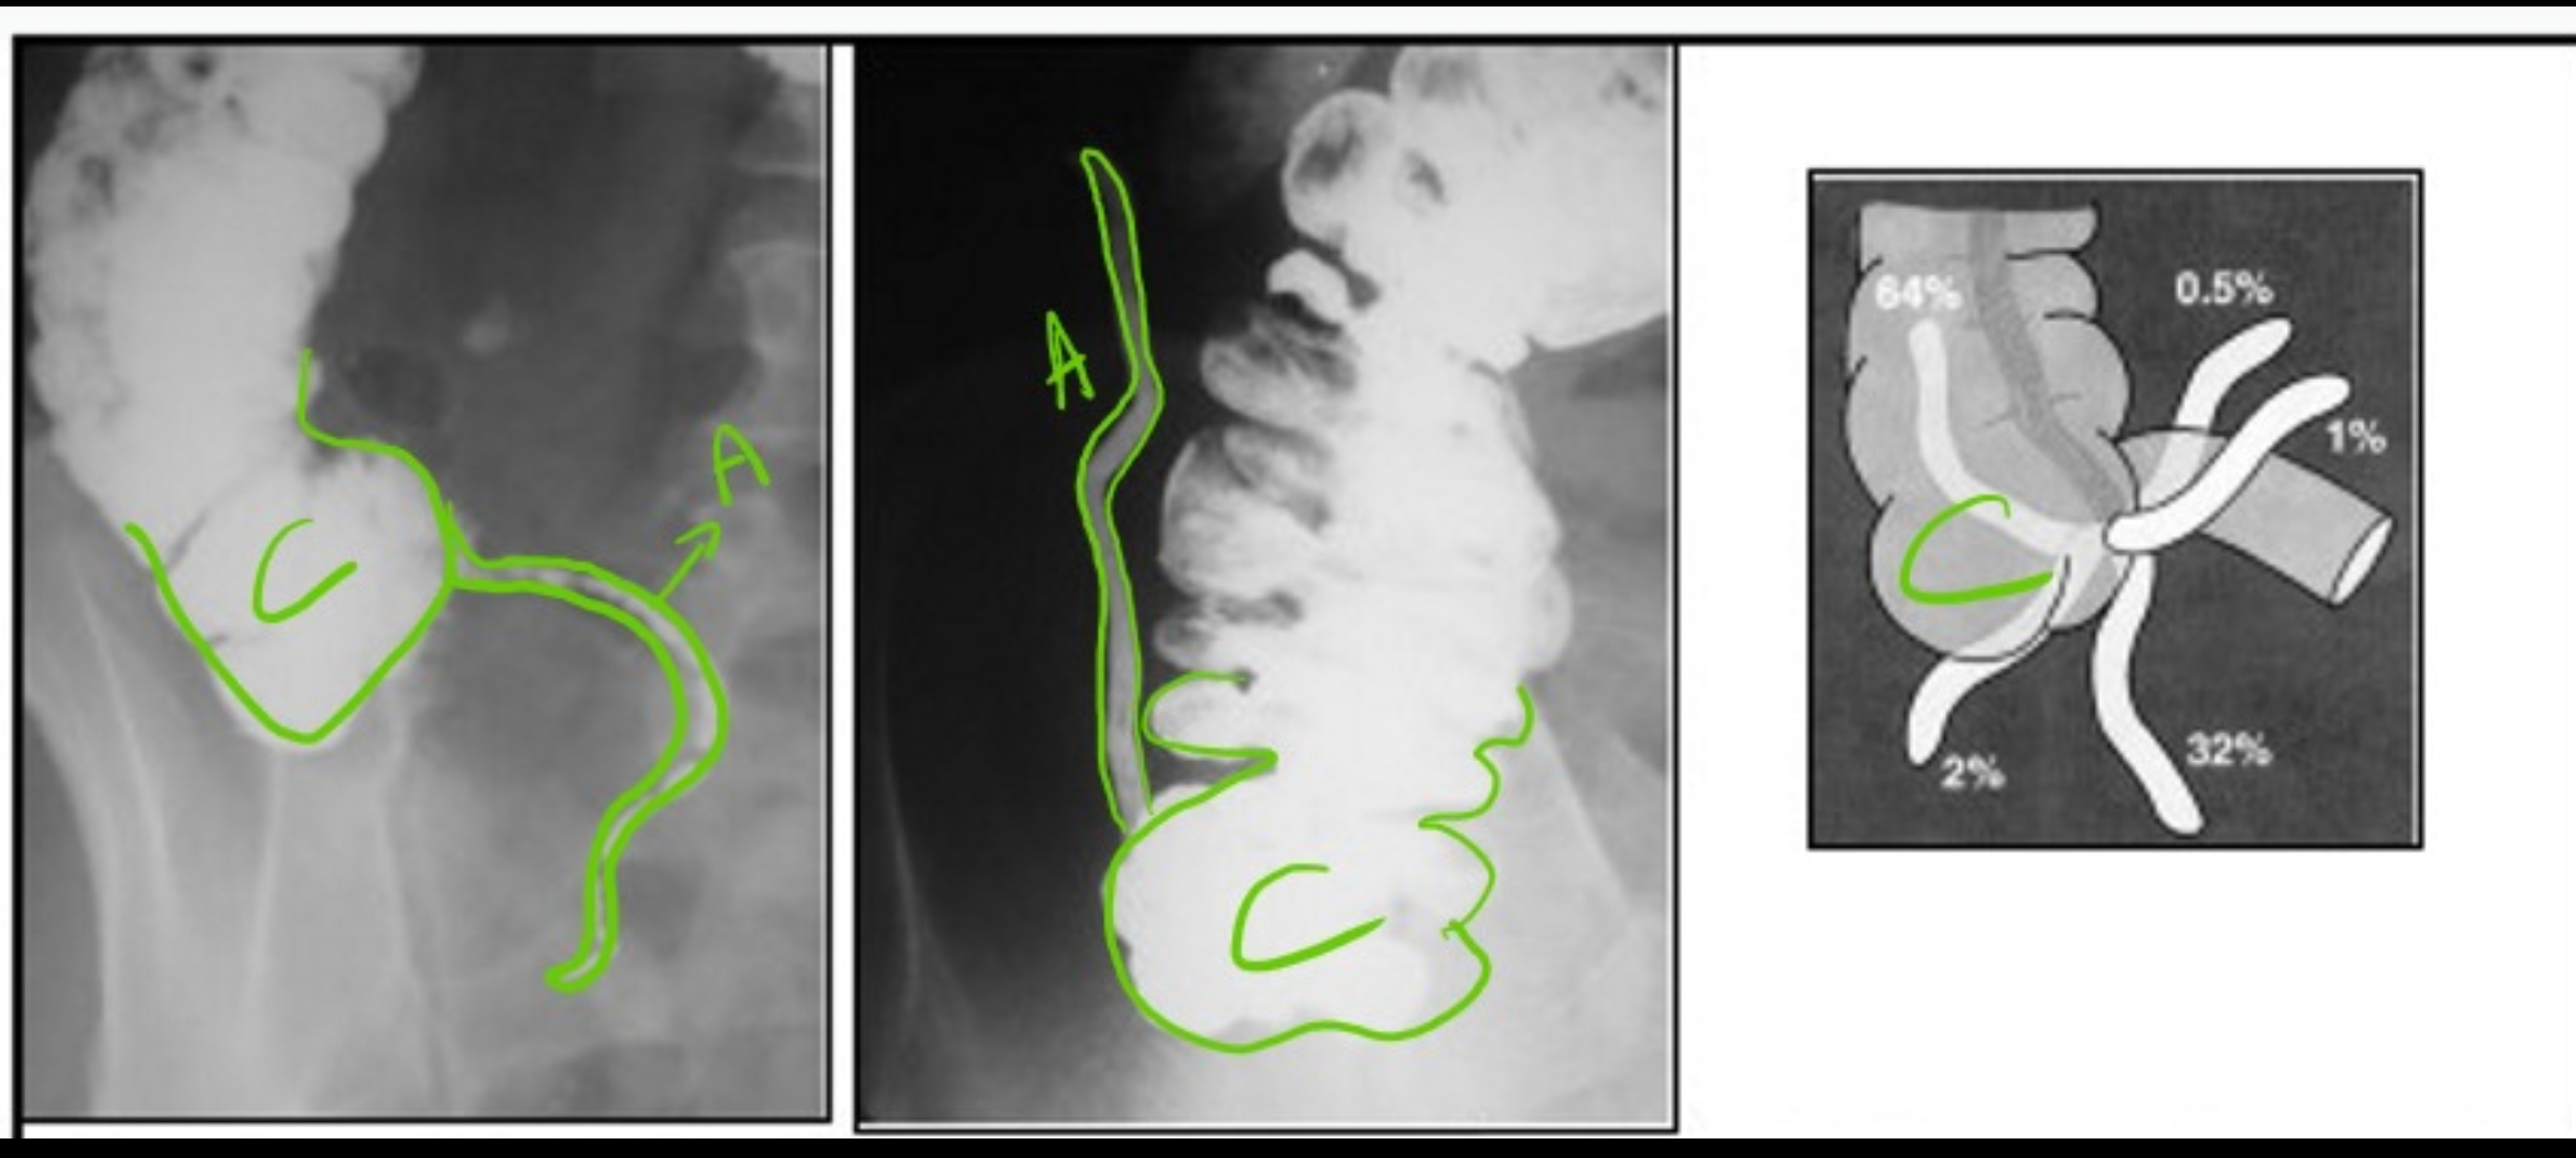

A = appendix vermiformis

(wormvormig aanhangsel)

C = caecum

(blinde darm)